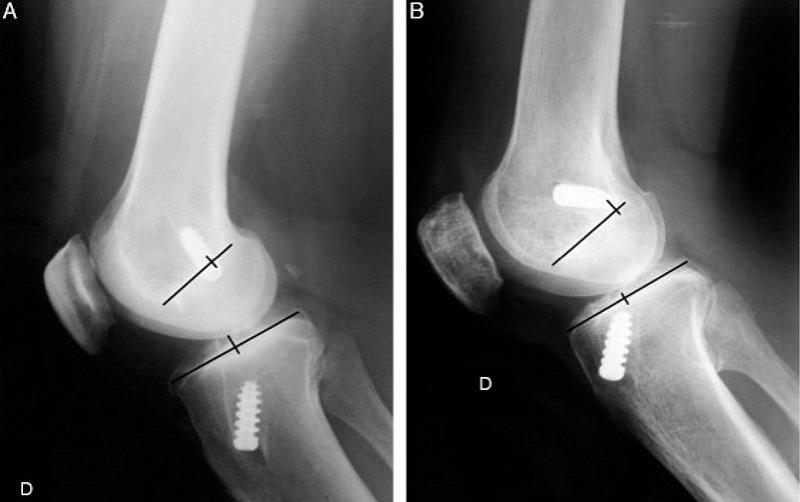

Para tanto, foi feito um estudo prospectivo e randomizado em bloco. Os pacientes foram submetidos a reconstrução do LCA por meio de duas técnicas: transtibial (grupo 1: 20 pacientes) ou de duas incisões (grupo 2: 20 pacientes). Foram avaliados o posicionamento radiográfico dos túneis, a inclinação do enxerto, a isometricidade do enxerto e os resultados funcionais (IKDC e Lysholm).

Considerando os resultados verificados, foi possível concluir que a técnica de duas incisões permitiu um posicionamento do túnel femoral mais lateralizado e anteriorizado e que o enxerto ficasse mais inclinado e demonstrou clinicamente um melhor resultado pela manobra de Pivot‐Shift. Não houve diferença na isometricidade e no resultado funcional final no curto tempo de seguimento avaliado.